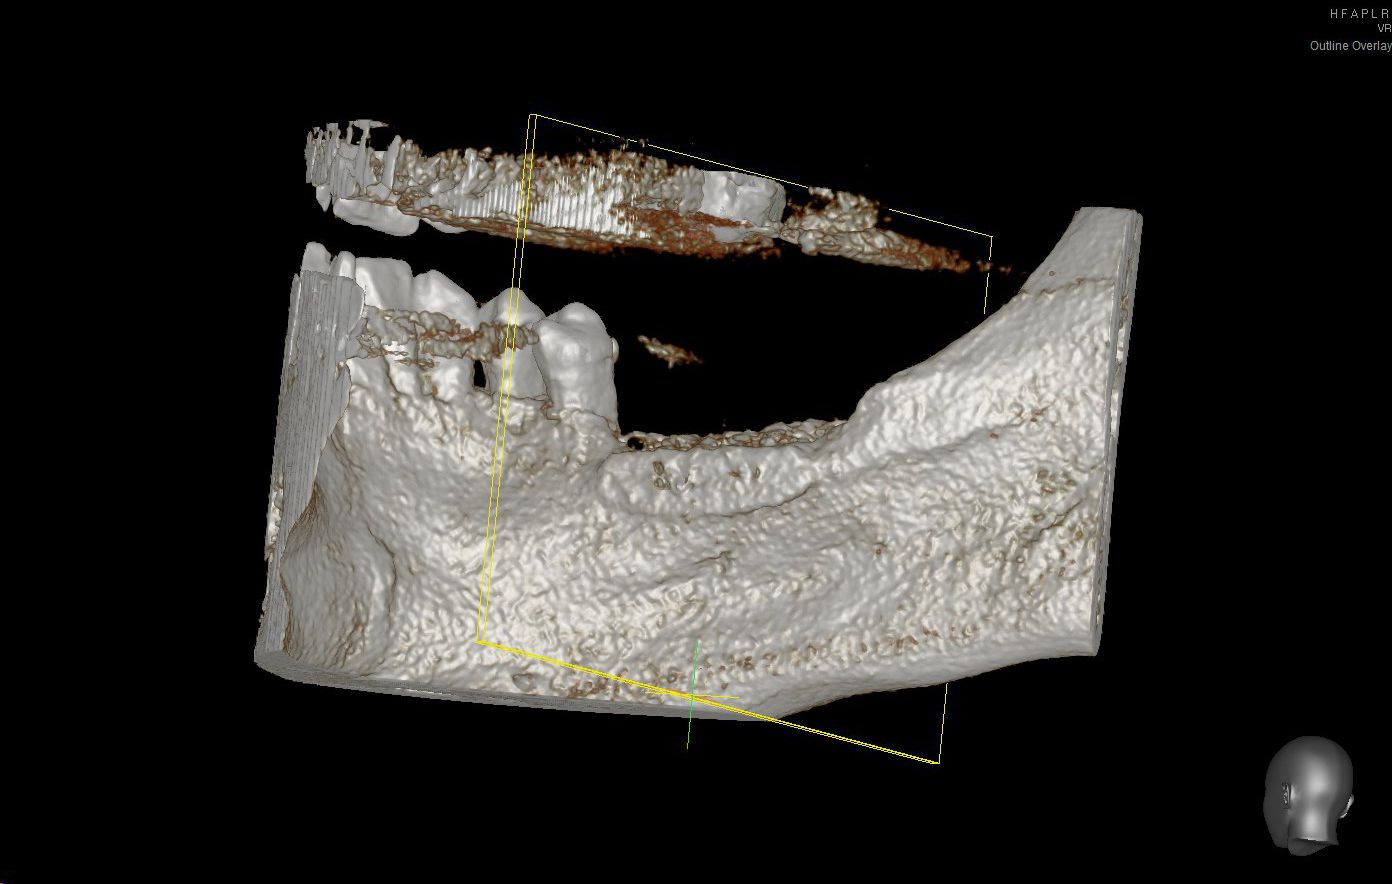

01/28 - Model of the initial defect computed from a CBCT scan - buccal viewThree-dimensional augmentation with maxgraft® cortico - Dr. R. Würdinger

Model of the initial defect computed from a CBCT scan - buccal view